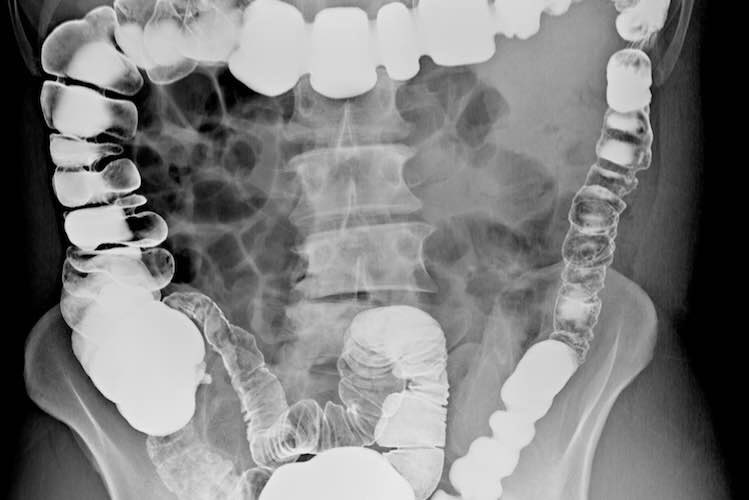

هو مرض مزمن يصيب الأمعاء الغليظة و يسبب تقلصات و انتفاخات في البطن (البطن منتفخ) ، يمكن أن يؤثر على أي شخص في أي عمر ، و تختلف أعراضه بين المصابين بهذا المرض و يُصنف هذا المرض ضمن منطقة الجهاز الهضمي كما هو موضح بالصورة:

الفحوصات و التشخيص اللازمة للقولون:

- اختبارات الأشعة